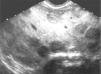

Al mes de edad las ecografías transfontanelar y cardíaca fueron normales y una ecografía renal confirmó la existencia de discreta ectasia piélica. Durante la realización de este último examen, se verificó la existencia de múltiples nódulos hepáticos hipoecogénicos, dispersos por ambos lóbulos, la mayoría de ellos de cerca de 2,5cm de diámetro (fig. 1); el estudio con modo Doppler mostró que estos nódulos estaban francamente vascularizados; los conductos biliares intrahepáticos y extrahepáticos tenían el calibre preservado; las venas suprahepáticas y la vena porta tenían dimensiones y flujo normales; bazo sin alteraciones; ausencia de adenomegalias o masas en el retroperitoneo. La alfa-fetoproteína sérica estaba elevada (441,5ng/ml; N < 1,5); hemograma y enzimas hepáticas normales; el estudio de coagulación era normal; catecolaminas y sus derivados en orina no presentaban alteraciones.